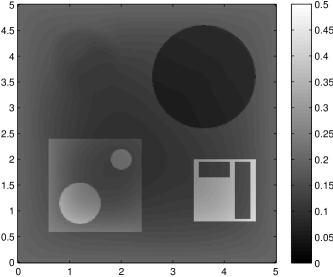

The edge detector is used to detect jumps in the derivatives of the data up to second order (to obtain an initial estimate of the parameter jump set ). Since this process is highly sensitive with respect to noise, we varied the edge detection procedure subject to the amount of noise in the data. In the noise-free examples, we estimated the jumps of all three functions , that is, jumps of derivatives of up to second order. We restricted the jump estimation to for the low-noise examples (i.e., jumps of derivatives up to first order) and in the high-noise examples (only jumps in the data itself).

Reconstruction results and error profiles at different noise levels can be seen in Figures 3 and 4. In both examples, the noise-free reconstructions are very accurate and contain mostly smoothing error. In the low-noise reconstructions, due to the fact that more regularization is necessary, some of the parameter variation is underestimated. In the high-noise examples, most detail in is lost since a lot of regularization is required to get reasonable results. The fine detail in can, however, still be recovered very accurately in both examples.